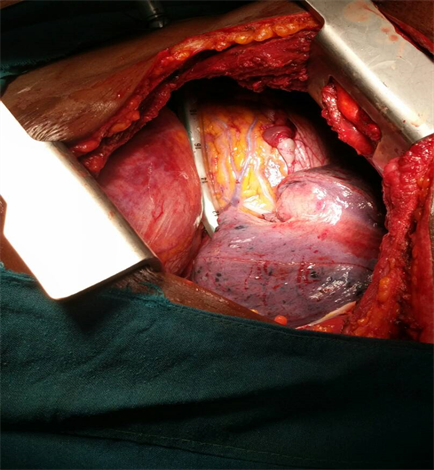

In the operating theatre, under general anaesthesia and double lumen intubation with size 39FG for isolation of the left lung and in right lateral decubitus position, a left standard posterolateral thoracotomy was performed entering the 7th intercostal space or pleural bed. There was approximately 900 mls of collected pleural blood, complete laceration of the pericardium extending from the diaphragmatic surface to the aortic root as shown in Figure 3, complete and thrombosed transection of the left pericardiophrenic artery, but intact coronary arteries and the coronary veins. The artery was ligated, the margins of the pericardium coagulated. Haemostasis was secured, the thoracic cavity irrigated with 1 litre of warm normal saline, a size 32 FG chest tube placed and the chest closed up in layers. The patient was extubated on table. He had uneventful course postoperatively with the removal of chest tube on the 3rd postoperative day and was discharged on the 8th postoperative day. He was followed-up at 2 weeks, one month and after 3 months concomitantly by the neurosurgeon, the ophthalmologist and at our clinic and has been well without any sequelae with intact vision, carrying out his daily activity.

Figure 3. Intraoperative picture showing the heart, the diaphragm, the edge of the ruptured pericardium with exposed vessels, chest tube and collapsed left lung.